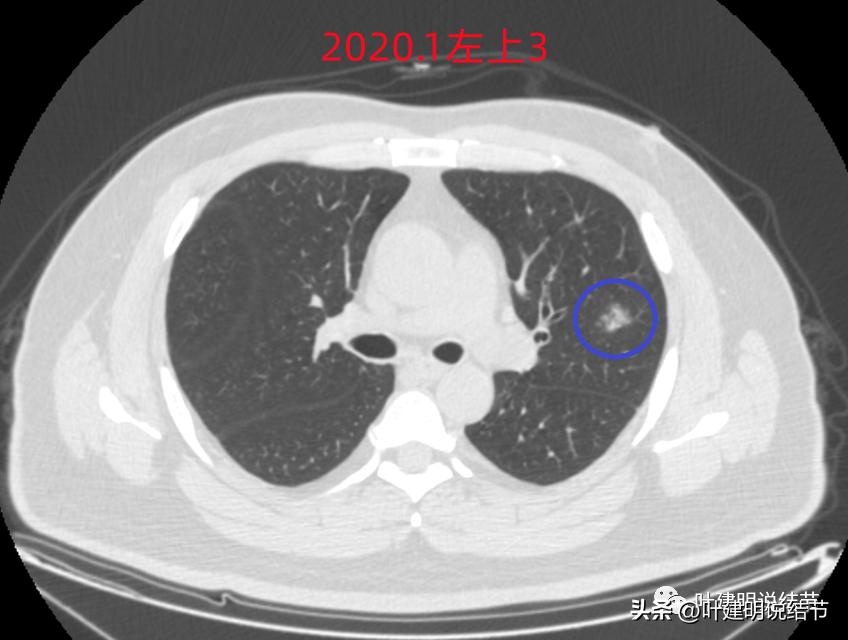

左上病灶3:混合磨玻璃结节偏实性,内部密度不均,整体轮廓清,有浅分叶,也有小血管关系密切,考虑浸润性腺癌可能性大;